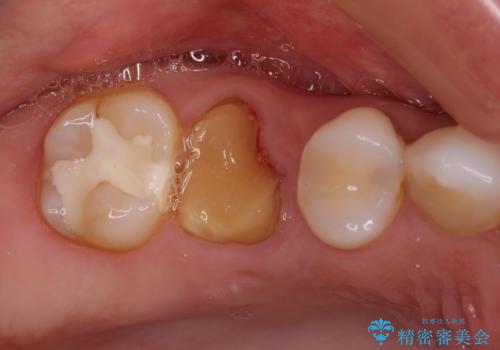

抜歯になった虫歯 奥歯のインプラント治療

強い咬み合わせで割れてしまった奥歯 インプラントによる咬合回復

虫歯による歯の喪失 インプラントによる咬合機能回復